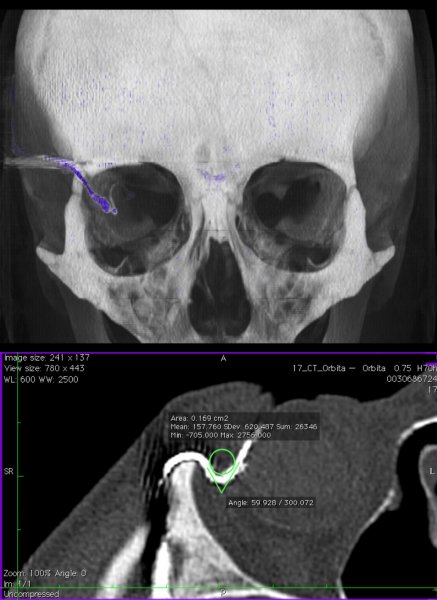

Wszczepienie implantu wiąże się ze skomplikowaną operacją mikrochirugiczną. Chip, umieszczany poniżej dolnych warstw siatkówki (która jest przezroczysta), połączony jest cienkim przewodem z cewką indukcyjną, znajdującą się za uchem. Przewód z gałki ocznej wyprowadzany jest do oczodołu, gdzie tworzy pętlę, a następnie, przez ścianę oczodołu, pod mięśniem skroniowym, prowadzony jest do przestrzeni zausznej. Tam wszczepiana jest cewka. Dzięki niewielkim magnesom, zakotwiczonym w kościach czaszki, możliwe jest przymocowanie drugiej cewki, tym razem na zewnątrz. Zasila ona implant oraz dostarcza informacje o zmianach kontrastu i jasności obrazu. Pacjent może regulować te parametry za pośrednictwem urządzenia wielkości telefonu komórkowego, które nosi w kieszeni.